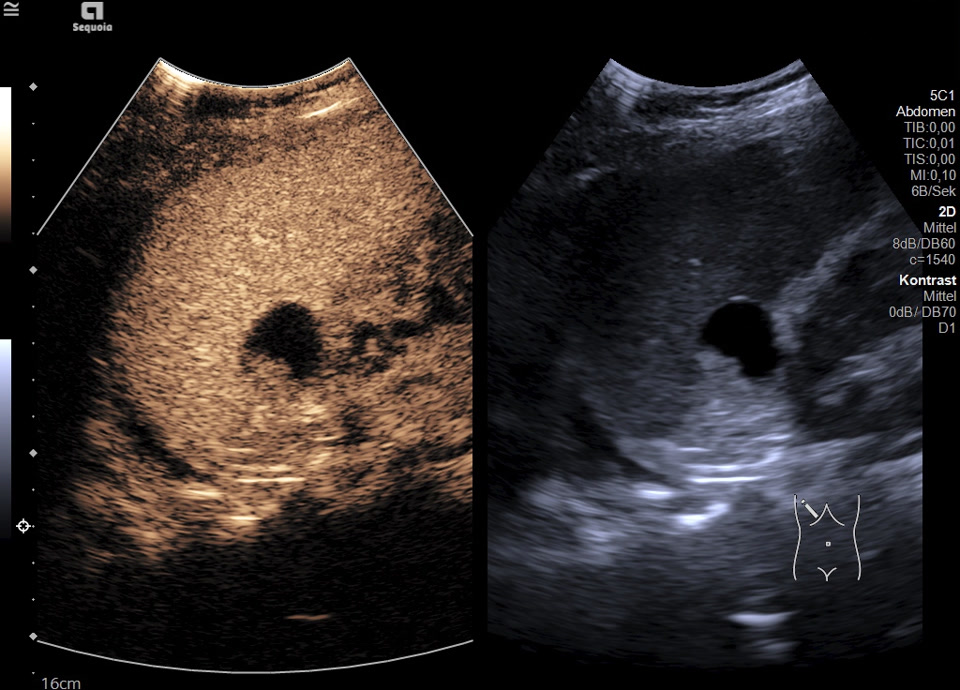

Es zeigt sich subkapsulär in Segment VI der Leber eine zystische Raumforderung mit durchgehendem Kapselreflex und hyperechogenem solidem Anteil. Der Befund ist nicht vereinbar mit einer blanden Zyste, sondern suspekt auf eine zystisch-solide Metastase. In der ergänzenden CEUS nehmen die soliden Anteile in der arteriellen Phase Kontrastmittel auf und zeigen in den portalvenösen sowie späten Phasen eine persistierende KM-Anreicherung ohne Washout. Zusätzlich finden sich eine noduläre Peritonealverdickung im Oberbauch sowie ein zystischer Ovarialtumor mit soliden Anteilen im rechten Unterbauch. In Zusammenschau der Befunde besteht der dringende Verdacht auf ein hepatisch und peritoneal metastasierendes Ovarialkarzinom.